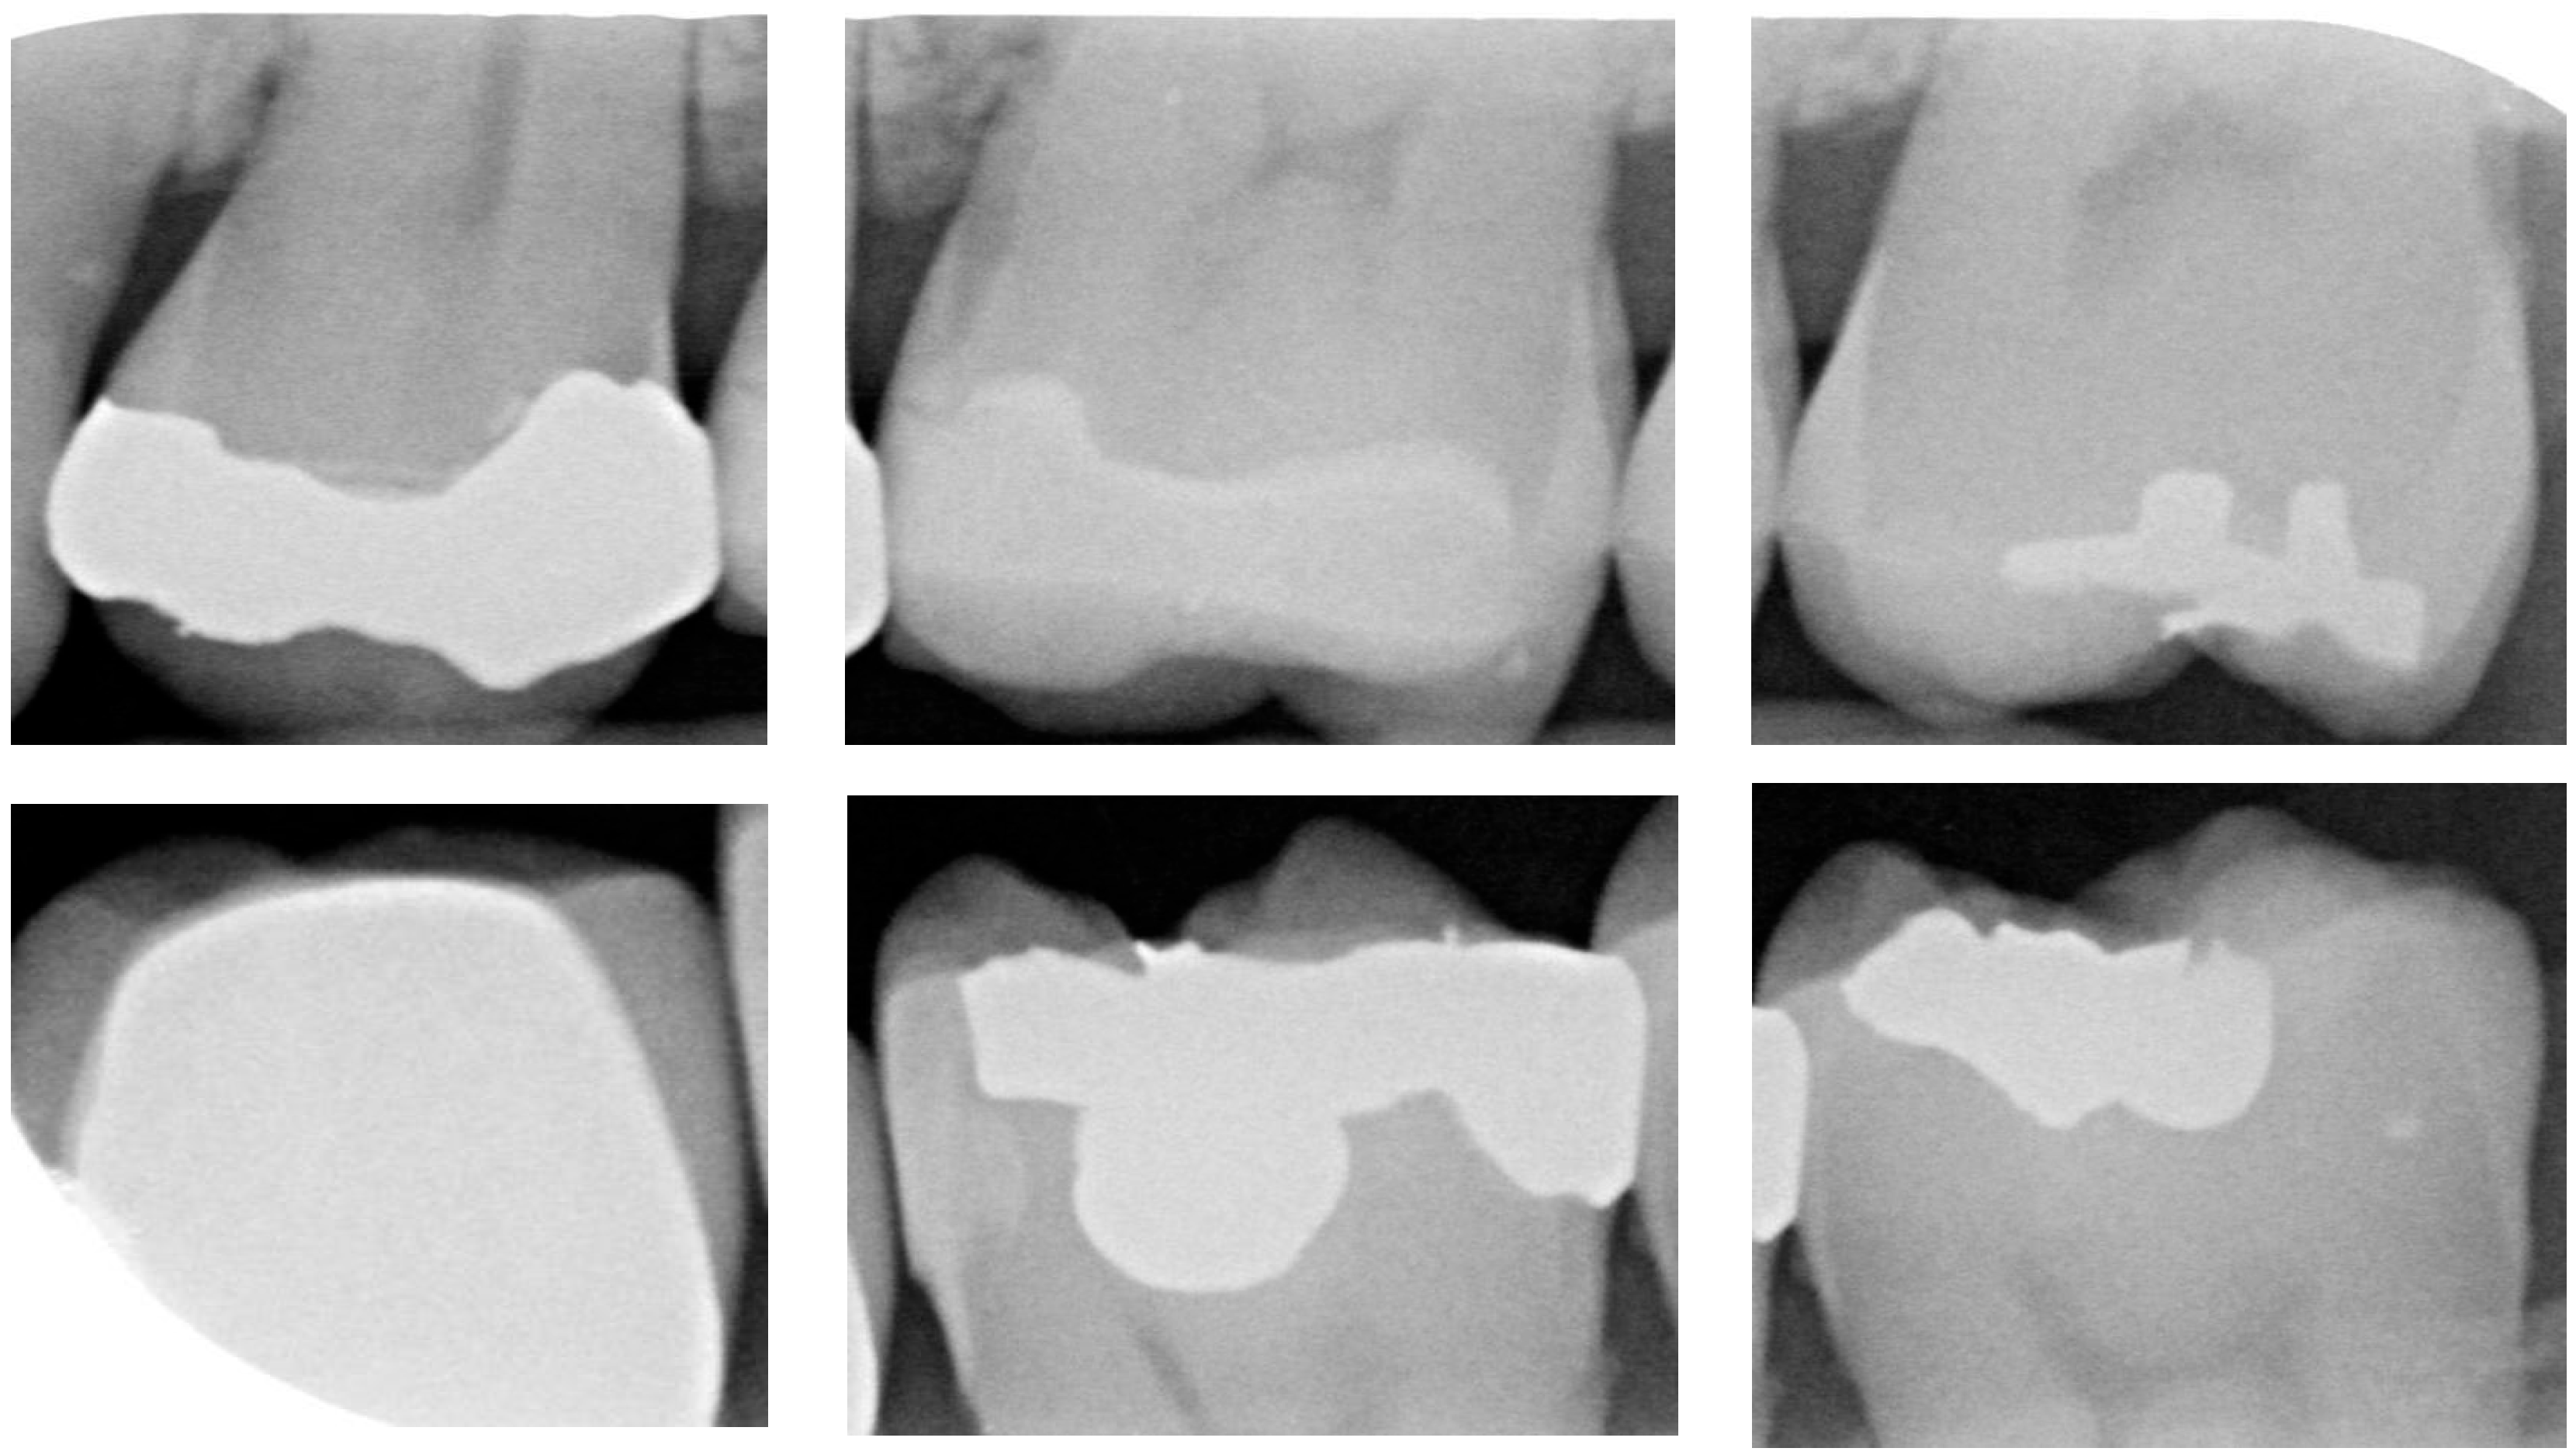

2.4.1. Dataset Augmentation

For CNN models, having an adequate amount of data is crucial to ensure effective learning and generalization performance. When the training sample size is limited, models are prone to overfitting or may fail to achieve good generalization performance. After applying the image-segmentation technique developed in this study, a total of 1340 images of individual teeth were obtained, including 428 images with dental calculus and 912 images without dental calculus. To balance the data quantity and to reduce overfitting issues, this study employed random image-flipping and mirroring techniques for data augmentation. This study set the dataset to include 670 images with dental calculus and 670 images without dental calculus. Dental calculus images were randomly selected for flipping or mirroring, while non-dental calculus images were also randomly selected to form the dataset for CNN training and validation. The detailed breakdown is presented in Table 4. A total of 80% of the image dataset was randomly chosen as the CNN training dataset. The remaining 20% of the dataset was used as the validation-image dataset. Moreover, the CNN training dataset was split into a 7:3 ratio for the training and testing datasets, and the training image as shown in Figure 9.

Figure 9.

Data augmentation results. (a) Dental calculus. (b) Without dental calculus.